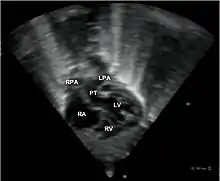

•Echocardiogram: An echocardiogram is an ultrasound of the heart that accurately assesses the heart’s structure and function, and can show the specific features of TGA, if present. This imaging modality allows for the definitive diagnosis of TGA to be made.[3]

Abbreviations: RA=right atrium, RV=right ventricle, LV=left ventricle, PT=pulmonary trunk, LPA and RPA=left and right pulmonary artery.